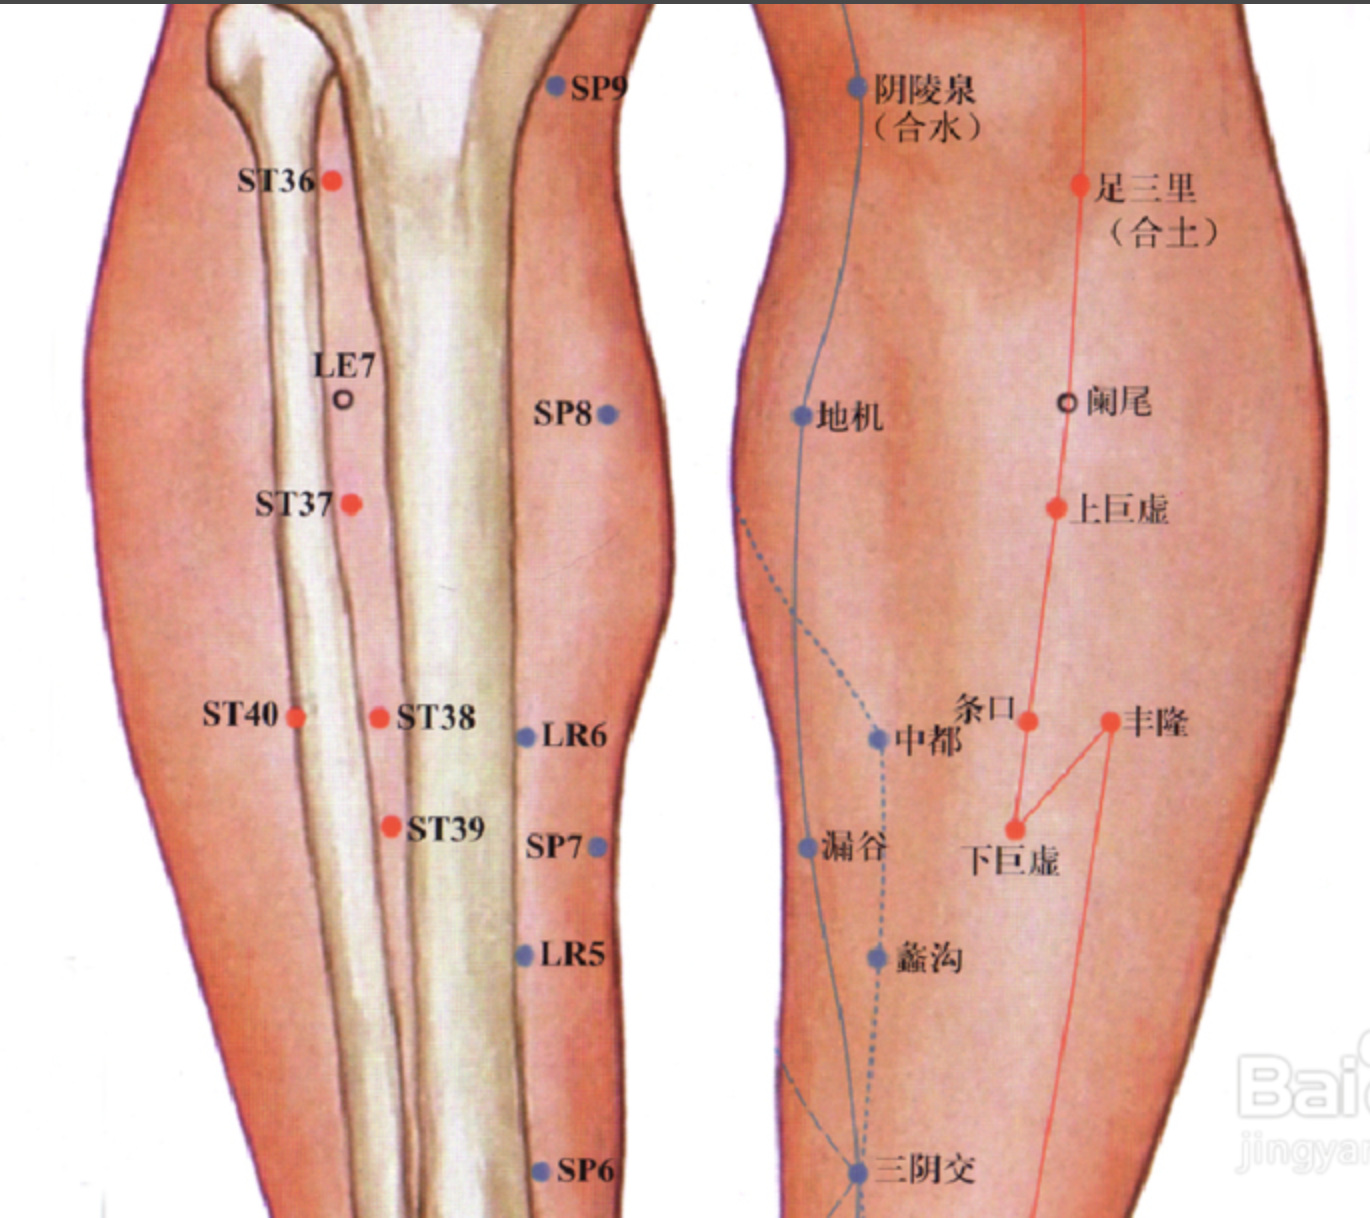

足三里

【定位】 在小腿前外侧,当犊(dú)鼻下 3 寸,距胫骨前嵴(jí)外 1 横指(中指)(图 10-21-4)。

【主治】 胃痛,呕吐,噎(yē)膈,腹胀,泄泻,痢疾,便秘,乳痈,肠痈,下肢痹痛,水肿,癫狂,脚气,虚劳羸(léi)瘦。

【配伍】 配中脘、梁丘治胃痛,配内关治呕吐,配气海治腹胀,配膻中、乳根治乳痈,配阳陵泉、悬钟治下肢痹痛,常灸足三里可养生保健。

【刺灸法】 直刺 1 ~ 2 寸,强身健体用灸法。

【附注】 (1)足阳明经所入为“合”;胃的下合穴。(2)本穴有强壮作用,为保健要穴。(3)参考资料:①据报道,针刺健康人和胃病患者的足三里和手三里,观察发现胃驰缓时针刺收缩加强,胃紧张时变为弛缓,并可解除幽门痉挛。②据报道,针刺单纯性消化不良和中毒性消化不良患儿的足三里、合谷、三阴交,可使原来低下的胃游离酸、总酸度、胃蛋白酶和胃脂肪酶活性迅速升高。③据报道,针刺人及家兔的足三里,发现裂解素(主要是裂解素含有大量多糖体的革兰氏阴性杆菌,也能灭活某些病毒)都有增加,人增加 17.85 单位,兔增加 62.1 单位,两者均在针后 12 小时增加最明显。④据报道,针刺家兔的“足三里”“大椎”可使其调理素明显增加,从而促进白细胞吞噬指数的上升,增强其免疫能力。

丰隆

【定位】 在小腿前外侧,当外踝尖上 8 寸,条口外 1 寸,距胫骨前嵴外 2 横指(中指)(图 10-21-4)。

【主治】 头痛,眩晕,痰多咳嗽,呕吐,便秘,水肿,癫狂,痫症,下肢痿痹。

【配伍】 配风池治眩晕,配膻中、肺俞治痰多咳嗽。

【刺灸法】 直刺 1 ~ 1.5 寸。

【附注】 足阳明经络穴。